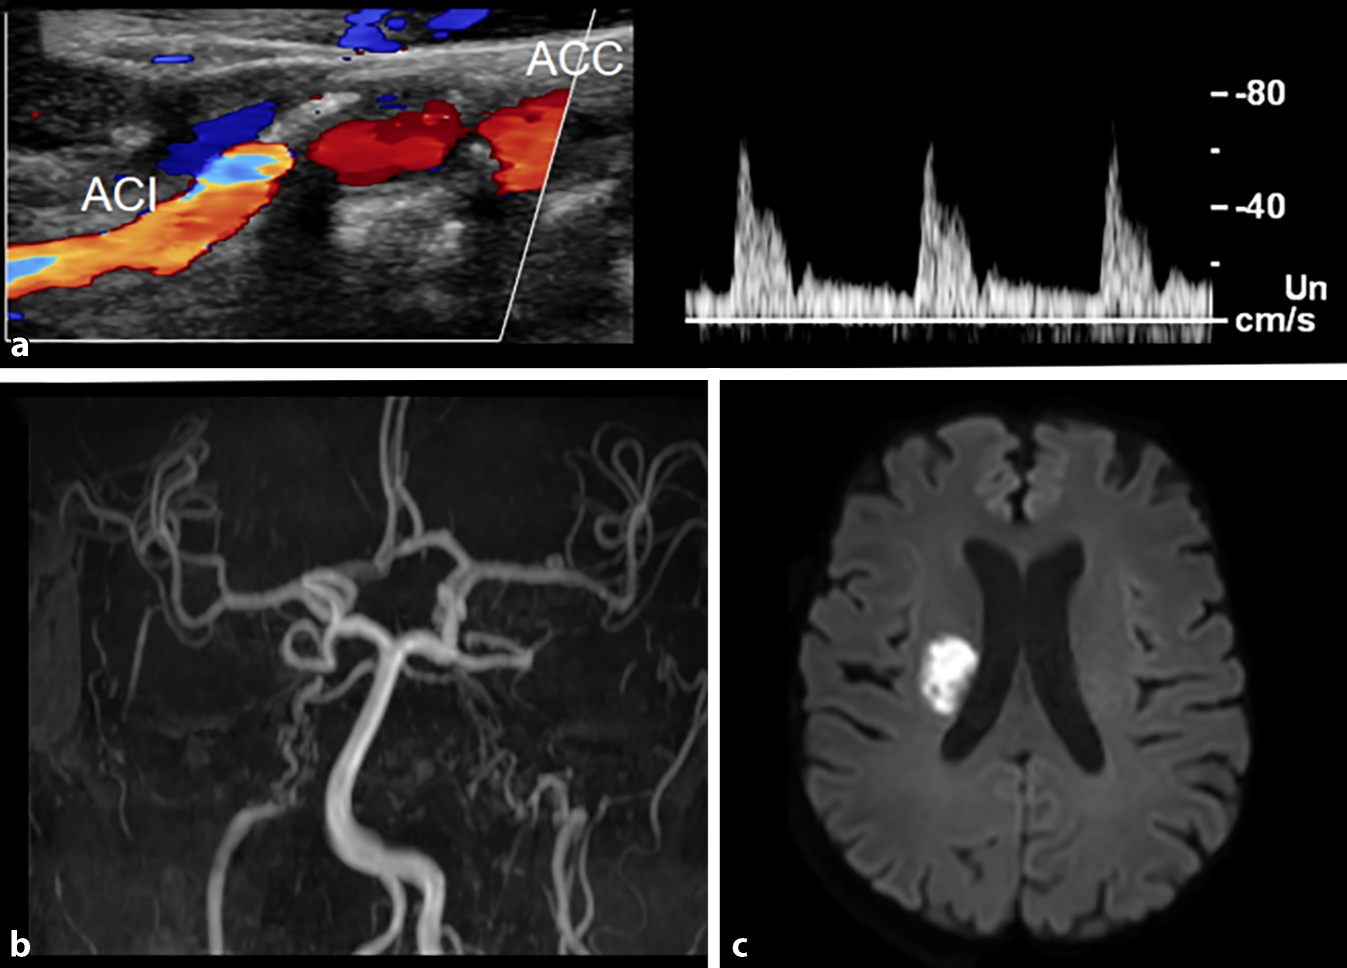

Ein 58-jähriger Patient stellte sich in unserer Klinik vor mit einer seit zwei Tagen bestehenden Sprechstörung und einer am Tag der Vorstellung aufgetretenen Gangstörung. Als Vorerkrankung bestand ein humangenetisch gesichertes Pseudoxanthoma elasticum (PXE). Im Rahmen der Erkrankung litt der Patient an typischen Hautveränderungen sowie einer peripheren arteriellen Verschlusskrankheit (pAVK IIb). In der neurologischen Untersuchung fanden sich eine leichte Dysarthrie und eine brachiofaziale Hemiparese links (NIHSS 3). Daneben zeigten sich die typischen Hautveränderungen des PXE (Abb. 1). In der CCT- und MRT-Bildgebung fand sich als morphologisches Korrelat der aktuellen Symptomatik ein rechtsseitiger Hirninfarkt im Nucleus caudatus und im oberen Anteil des Linsenkerns. Daneben ließen sich ältere Infarktresiduen im rechten Thalamus, in der Pons links paramedian sowie zerebellär im Stromgebiet der A. cerebelli inferior posterior nachweisen (Abb. 2). Die MR-Angiographie dokumentierte beidseits ein Rete mirabile der distalen A. carotis interna extrakraniell. Kompensatorisch waren beide Vertebralarterien sowie Aa. communicantes posteriores kräftig ausgebildet. Daneben bestand eine hochgradige Abgangsstenose der A. vertebralis links im V1-Segment. Farbduplexsonographisch fanden wir reduzierte Flussgeschwindigkeiten in der A. carotis interna extrakraniell beidseits bei geringem Gefäßkaliber (Abb. 2) mit kräftiger intrakranieller Kollateralisierung über die Rr. communicantes posteriores. Die übrige Hirninfarktabklärung inklusive Ruhe- und LZ-EKG sowie transösophagealer Echokardiographie blieb ohne wegweisende Befunde.

a Farbduplexsonographie der A. carotis interna (ACI) und A. carotis communis (ACC) rechts und Dopplerfrequenzspektren der ACI. Plaque am Abgang der schmächtigen A. carotis interna, die Flussgeschwindigkeit relativ niedrig und pulsatil. b „Maximum intensity projection“ einer 3‑D-Time-of-flight-Angiographie in koronarer Schnittführung, Abbruch der ACI beidseits und angedeutete Darstellung des Rete mirabile. c Diffusionsgewichtete Darstellung (isotrope Darstellung, b‑Wert: 1000), isotrope (richtungsunabhängige Darstellung), Nachweis einer Diffusionsstörung rechts paraventrikulär